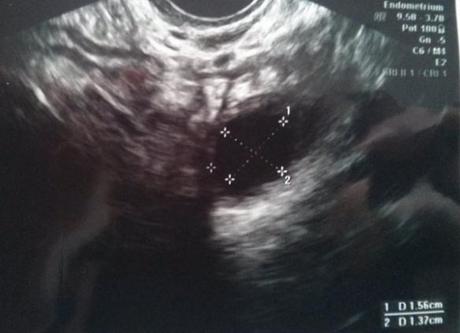

En esta foto tenéis el ovario izquierdo con un folículo solitario.

En el ovario izquierdo había sólo un folículo pequeño, por lo que a simple vista, según la ginecóloga, estoy respondiendo bien al Omifín, era evidente que no había ovulado todavía y nos volveríamos a ver el viernes para otra ecografía de control.